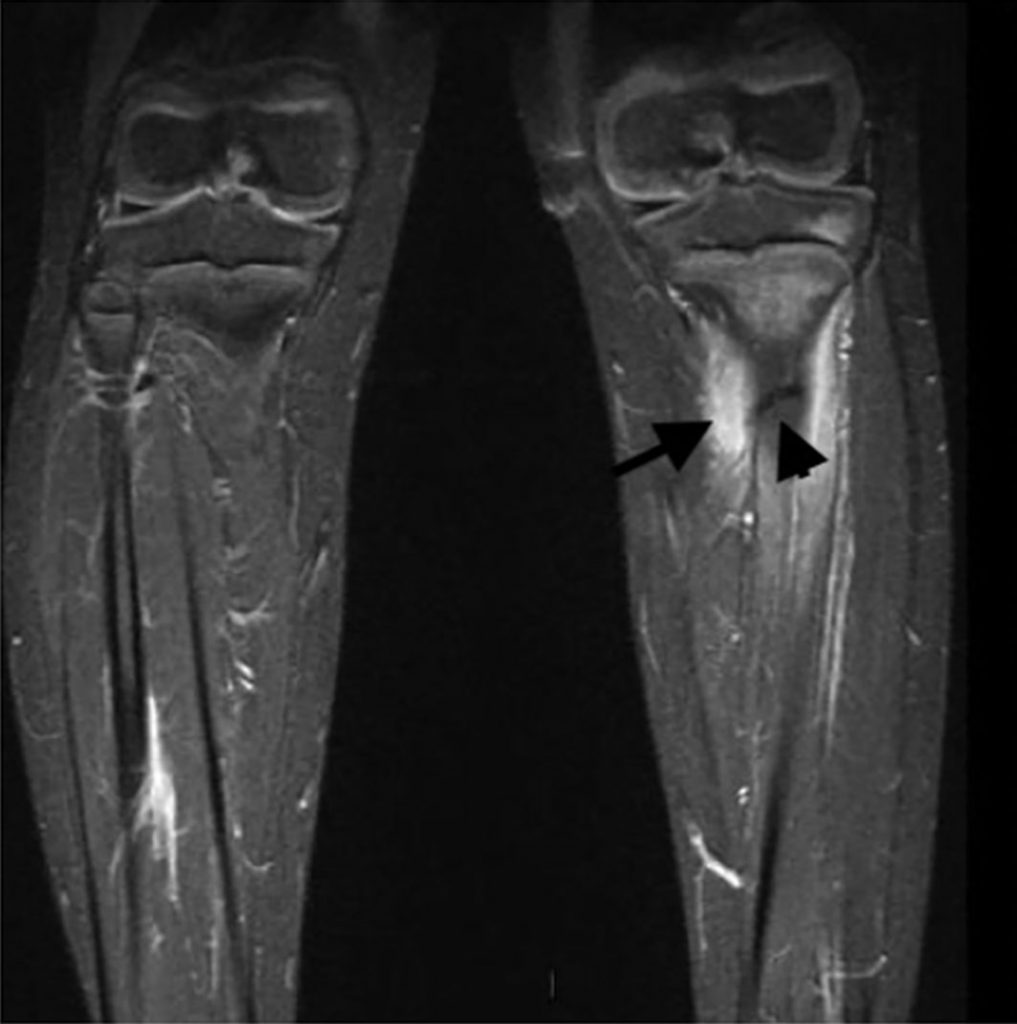

L’IRM, lorsqu’elle est facilement accessible et que l’enfant est coopérant (plus de 5 ans), est l’imagerie de complément à privilégier pour mettre en évidence une fracture de fatigue (figure 115.5), le plus souvent non visible sur les premiers clichés radiographiques.

Fig. 115.5 IRM des jambes. Enfant de 7 ans présentant une impotence fonctionnelle du membre inférieur gauche et une douleur après une randonnée.

La radiographie de jambe était normale. L’IRM (coupe coronale STIR) sur les deux jambes montre le trait de fracture du tiers supérieur de la diaphyse tibiale gauche en net hyposignal (tête de flèche) associé à des appositions périostées en hypersignal (flèche).

Source : CERF, CNEBMN, 2022.